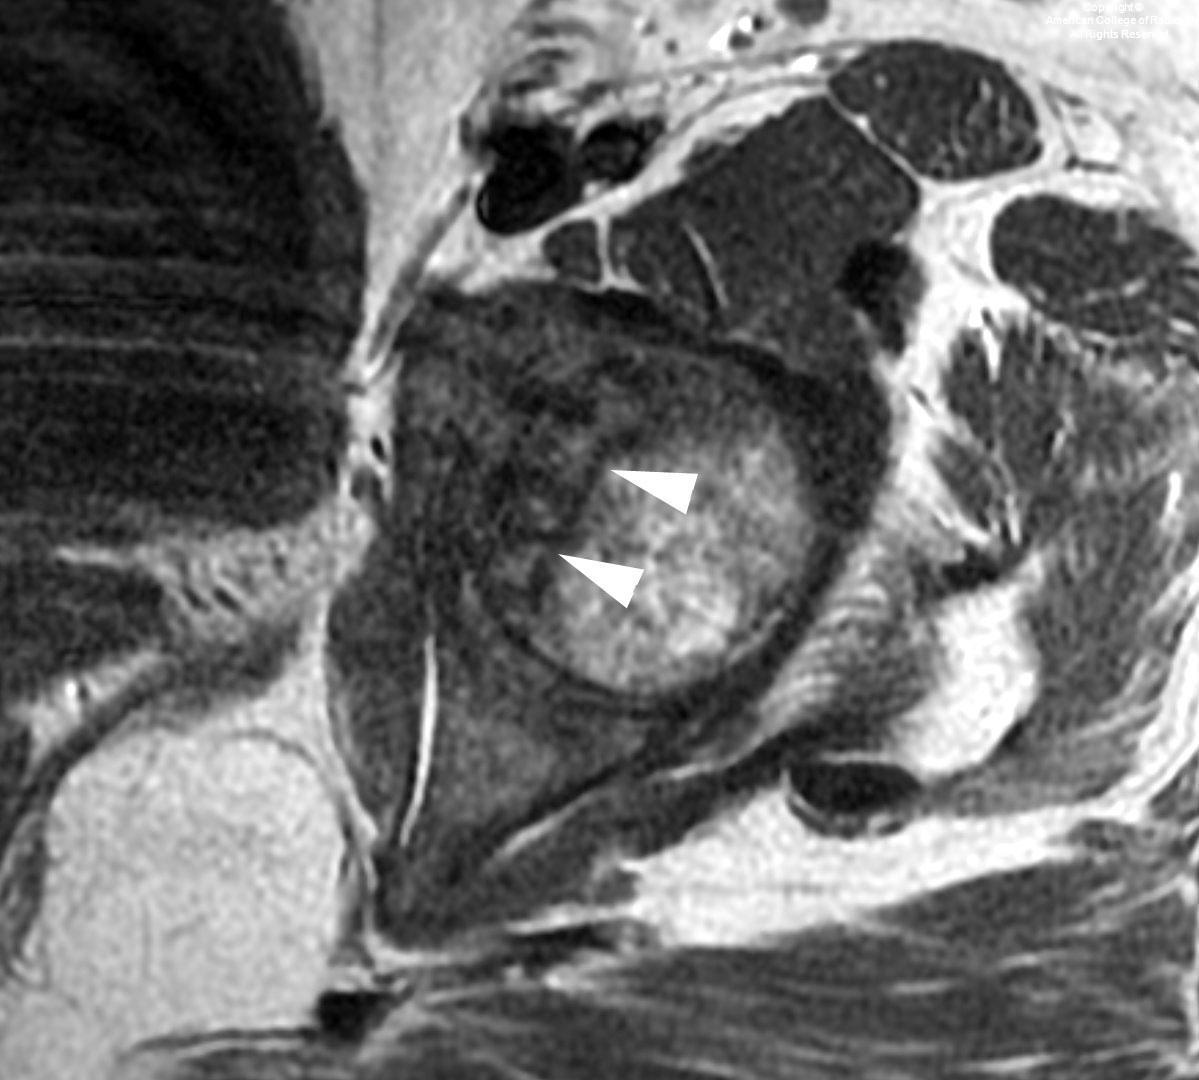

Typical MR appearance of AVN

• T2 or PD hyperintense - hyperemia and granulation tissue

• T1 hypointense margin - linear sclerosis